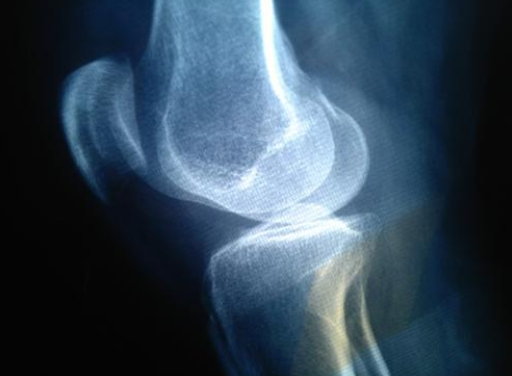

此外通过做X光片的检查,如果骨骺还没有完全闭合的话,说明还有增高的空间。